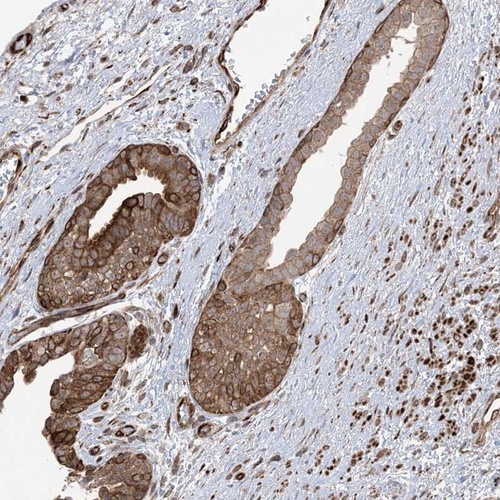

Immunohistochemical staining of human prostate shows distinct cytoplasmic, membranous and nuclear positivity in glandular cells.